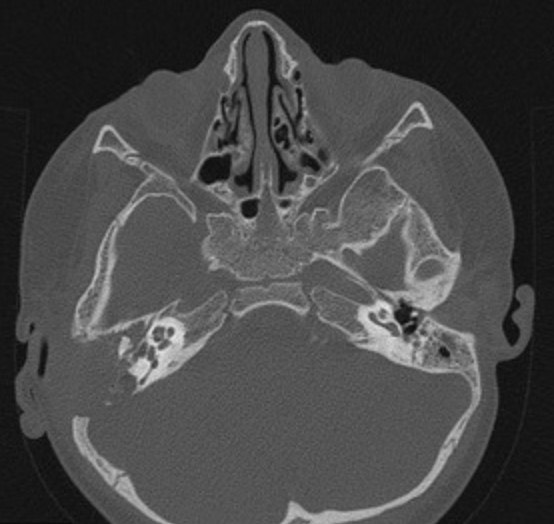

1966. У пациента с выявленными на компьютерной томограмме множественными рентгенопрозрачными очагами в костях основания черепа, плохо отграниченными от окружающих тканей, вероятной природой изменений считают